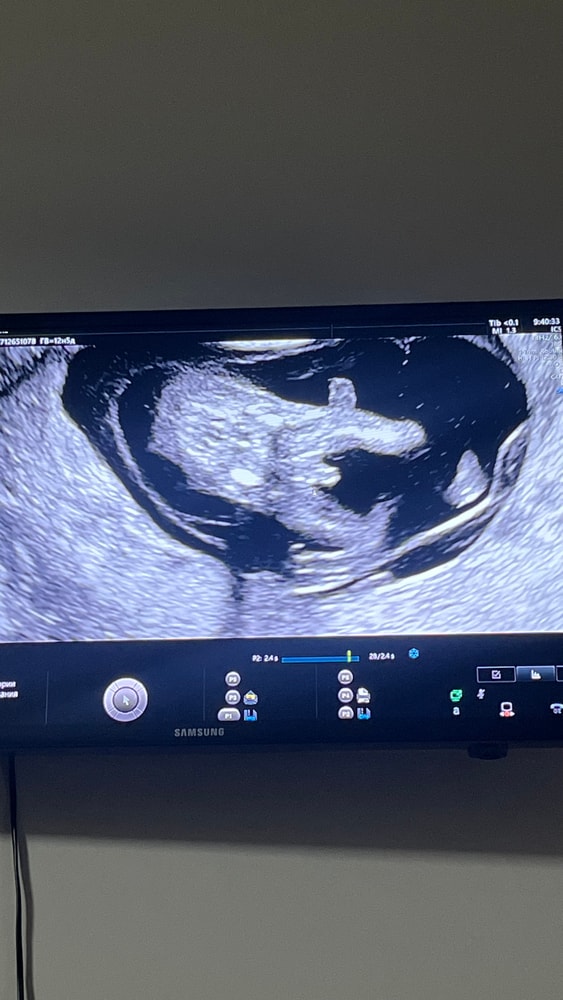

По узи срок 13 недель. 3 фотка предположили, что мальчиковые половые органы, на 1/2 фотке ничего вроде бы не видно(только пуповина). Как думаете узист ошиблась? Хотя уверена вроде говорила… Оч хочу дочу, снилась мне вчера, а тут я ошарашена новостью. Девочка до беременности снилась и я прям чувствовала, что мне надо за ней. Решилась как видите на 1 беременность и тут такое. У вас путали с пуповиной пол? Поделитесь своими историями…

Это не тот ракурс, в котором можно на вашем сроке определить пол- на вашем сроке его определяют только предположительно по направлению полового бугорка относительно позвоночника. А сам размер и форма бугорка и половых складок еще одинаковы у мальчика и девочки.

С этого ракурса на таком сроке не смотрят. Придется набраться терпения и подождать ещё пару- тройку недель. Я за девочку))) тоже была уверена, что будет дочь, но родился сын, а дочь вторая)